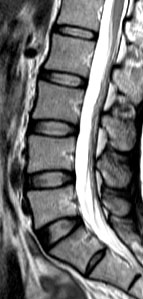

The current study was a cross-sectional assessment of adults from this cohort who were 21 years of age and older. A total of 2,599 individuals were assessed with magnetic resonance imaging (MRI). Amongst them, 27% (n=709) did not have disc degeneration while 73% (n=1,890) had. Of the subjects who have disc degeneration, 7% were underweight, 48% were in the normal weight range, 36% were overweight, and 9% were obese. Overweight and obese individuals were also found to have a greater extent and severity of disc degeneration in comparison to those individuals of normal weight or underweight.